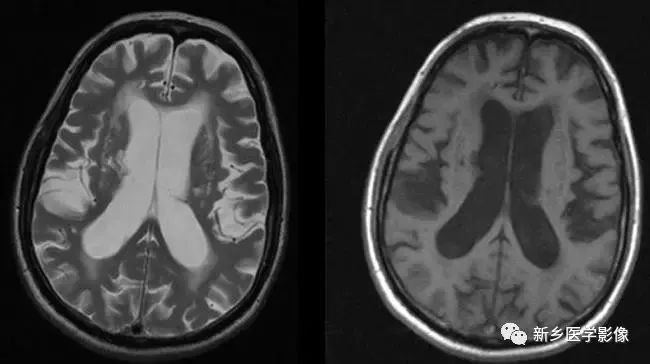

侧脑室局部扩大

❶ 局限性脑萎缩

外伤后脑萎缩、感染后脑萎缩、脑梗死后脑萎缩:

CT可见扩大的脑室部分附近的脑实质呈片状低密度灶;MR可见T1WI呈低信号,T2WI呈高信号。同时脑沟及蛛网膜下腔增宽。